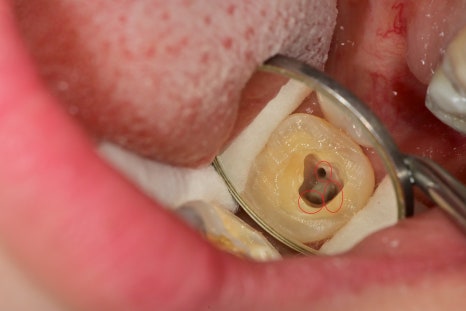

좌측 아래 맨 끝 어금니의 수복물이 떨어져 있습니다.

치아의 맨 끝부분이 깨져나가있으며

역시 뿌리 안쪽까지 크랙이 이어져 있습니다.

다시 비슷한 치아의 신경관 구조를 보면

실제 치아 내에서도 단독으로 입구가 존재하기도 하지만

계곡을 이루듯 신경관들이 연결이 되어있어서

최대한 많은 입구를 확보하는 게 가장 중요합니다.